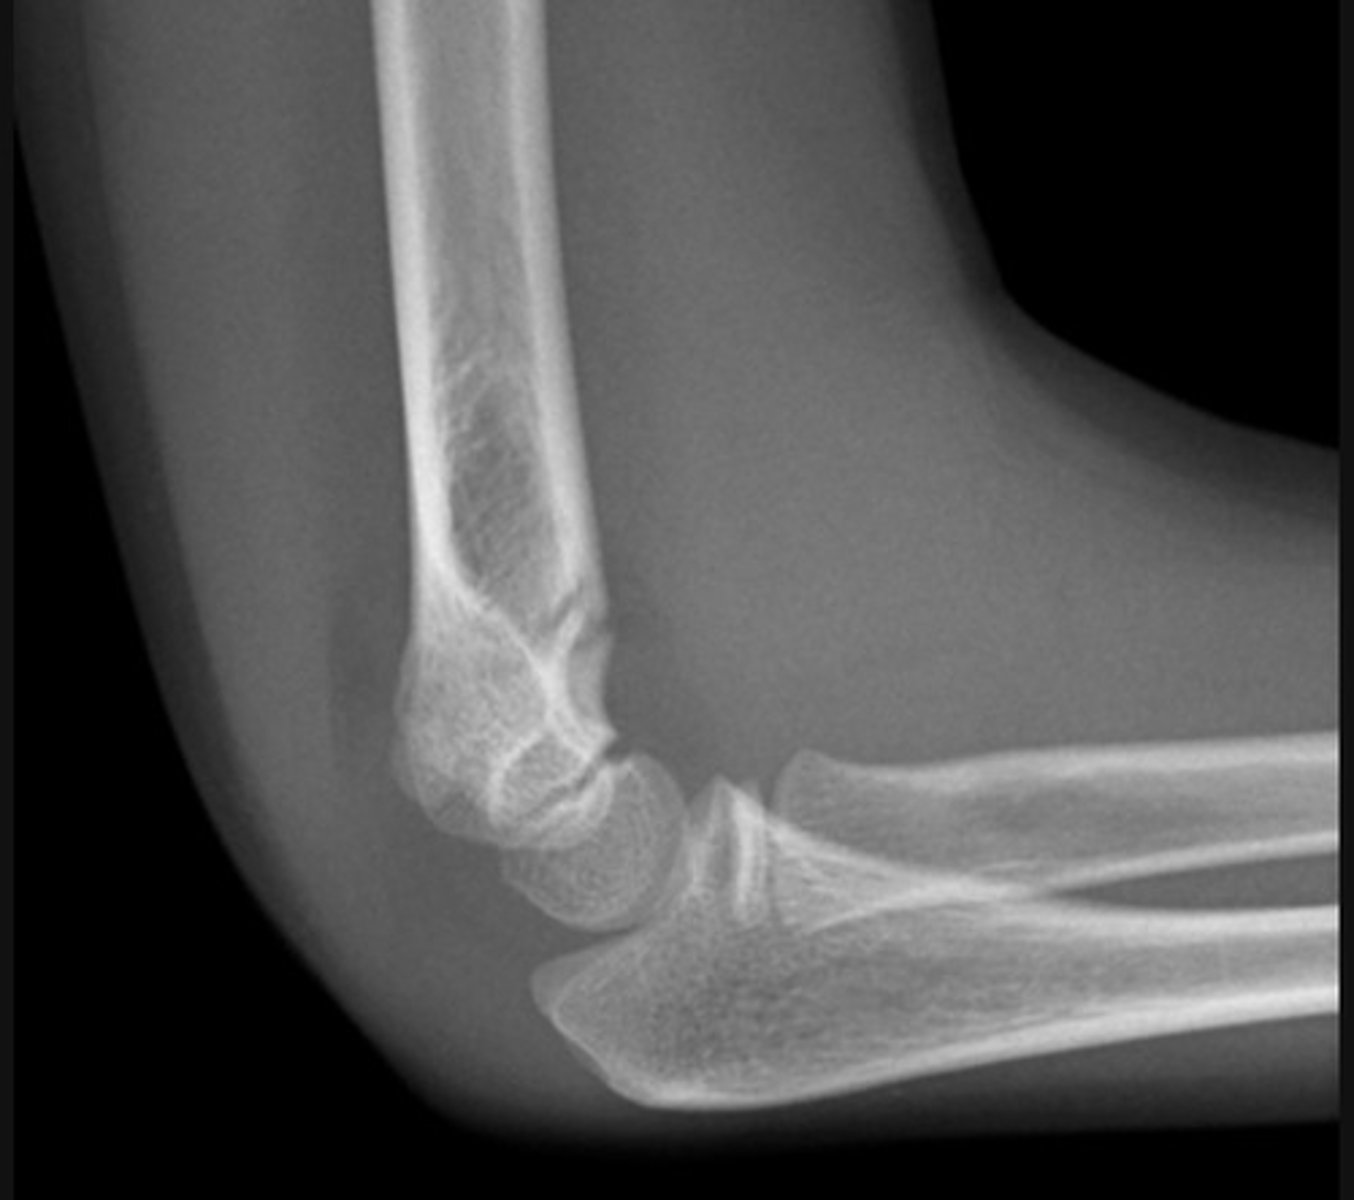

Supracondylar fracture - Lateral

This is the commonest elbow fracture in children

A joint effusion raises the anterior and posterior fat pads, indicating intra-capsular injury

Less than one third of the capitulum of the humerus lies in front of the anterior humeral line

The distal fracture fragment is pulled posteriorly by the triceps muscle

The fracture line is not visible on the lateral view in this case

The effusion - indicated by raised fat pads - is the only visible sign of injury and in the context of trauma should be taken to indicate an undisplaced intra-capsular fracture